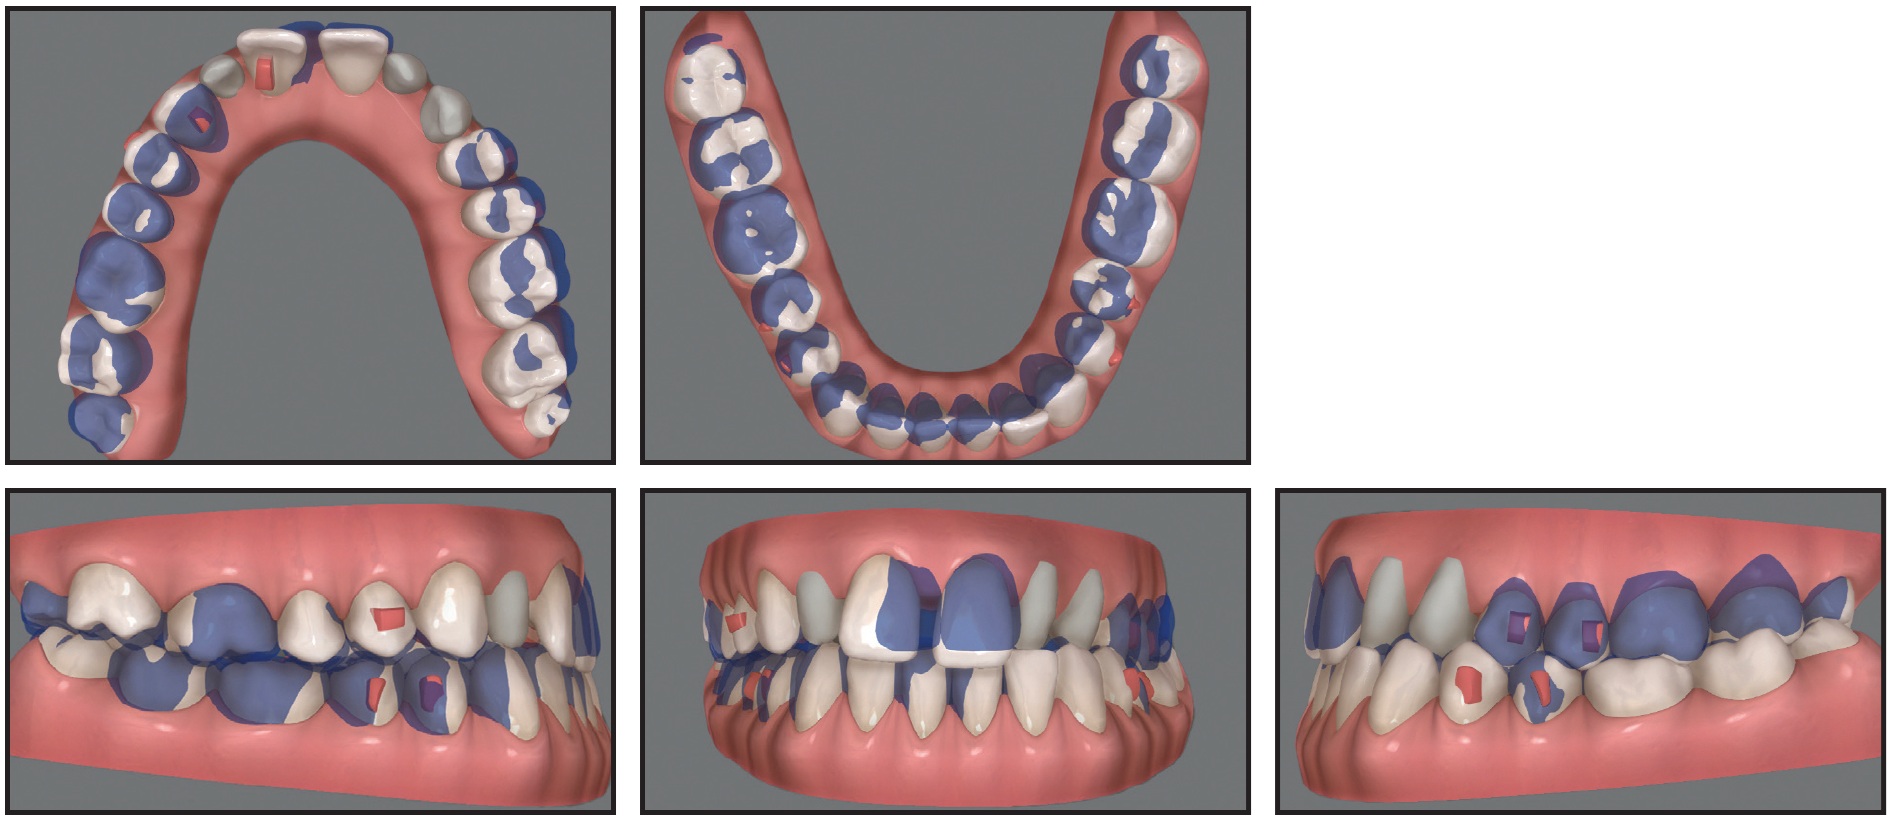

Case 3: Applying Traction Forces with Different Vectors

A 29-year-old male presented with the chief complaint of a gap between his upper front teeth (Fig. 11). The soft-tissue profile was straight, with mildly retrusive upper and lower lips, 50% incisor display in smiling, and a flat smile arc. The mandibular midline was deviated 3mm to the left of the facial midline, and there was a 2mm diastema between the upper central incisors; the overbite was 1-2mm. Class III molar and canine relationships were present on the right side, and Class I relationships on the left. The maxillary arch was constricted compared to the mandibular arch, with a crossbite from the left canine to the left second molar. The lower left deciduous canine was retained, and mild crowding was noted in the mandibular arch. The upper right lateral incisor was in an edge-to-edge relationship with the lower right canine, while the upper left incisor was in an anterior crossbite. Bolton analysis indicated a 2.07mm mandibular excess due to the narrow mesiodistal width of the upper lateral incisors (6mm each).

Fig. 11 Case 3. 29-year-old male patient with horizontally impacted upper left canine, diastema between upper central incisors, Class III molar and canine relationships on right side, left buccal crossbite, and Bolton discrepancy before treatment.

The panoramic radiograph revealed that the upper left canine was horizontally impacted, overlapping the root of the upper left lateral incisor. Cephalometric analysis indicated a Class III skeletal relationship (ANB = –1°, Wits appraisal = –3mm) with a normal vertical dimension (MPA = 34°). Both the upper and lower incisors were retroclined.

Treatment objectives were to bring the impacted canine into the arch and obtain Class I molar and canine relationships, along with a normal overjet and overbite. The Bolton discrepancy would be addressed with porcelain veneers on the upper lateral incisors. The goals of clear aligner treatment (see box) were to expand the maxillary arch, procline the incisors, close the space between the upper central incisors, prepare space in the arch for the impacted canine, and correct the Class III relationship and midline deviation, using Class III elastics for bite stimulation (Fig. 12).

Fig. 12 Case 3. ClinCheck superimposition of initial (white) and planned (purple) tooth movements for first set of aligners.

The impacted canine was exposed using the closed surgical technique, and a distal force vector was applied immediately to upright the tooth while moving it away from the lateral incisor (Fig. 13).

Four months after traction began, the canine crown had erupted into the arch. A vertical force vector was applied using 3⁄16", 4.5oz vertical elastics, worn at night from a lingual button on the canine to an undercut on the labial side, and 1⁄8", 4.5oz elastics, worn during the day from the button to the opposite arch.

After 14 months of treatment, three-quarters of the canine was exposed. Refinement trays were delivered to begin the derotation. The lingual button was then removed, and a lingual vertical attachment was bonded for aligner retention (Fig. 14).

Fig. 13 Case 3. Elastomeric chain tied from impacted canine to first molar to apply distal force vector.

Fig. 14 Case 3. ClinCheck plan of refinement stage, with lingual attachment used to derotate canine.

After 30 months of treatment, involving 27 sets of aligners for the initial treatment and five sets for refinement, changed every two weeks, the left canine was fully aligned, and proper torque and root parallelism were obtained, with no signs of root resorption noted on the panoramic radiograph (Fig. 15). The upper lateral incisors were restored with porcelain veneers. The appearance of the smile had improved, with increased incisor display. The lower midline was coincident with the facial midline, and Class I canine and molar relationships were achieved.

Fig. 15 Case 3. Patient after 30 months of treatment, showing aligned upper left canine, Class I canine and molar relationships, and improved smile appearance.